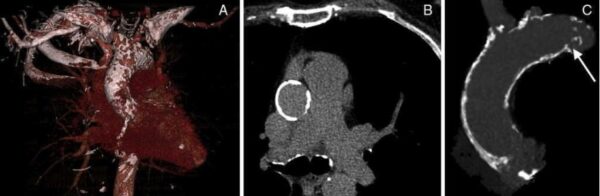

2. Cuantificación de Calcificación valvular aórtica:

En segundo lugar, es muy importante cuantificar la severidad de la calcificación valvular. Tambien, se debe de determinar si la válvula aórtica es bivalva o trivalva (muy importante cuando existe dilatación aneurismática de la aorta ascendente).

calcificacion de aorta bivalva sievers

5. Valorar la aorta ascendente

Al mismo tiempo, se puede realizar una valoración de la aorta ascendente para definir el ángulo del cayado aórtico. Valorar su calcificación “aorta en porcelana” y sus diámetros “aneurisma” de aorta.

aorta en porcelana tac de corazon